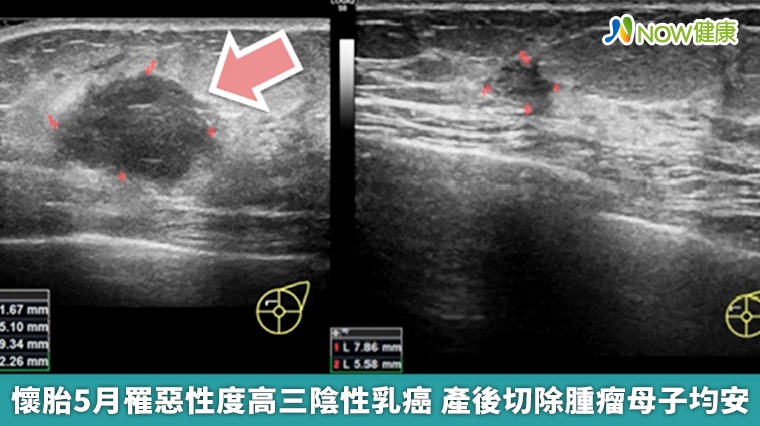

▲中國醫藥大學附設醫院乳房外科團隊指出,周女士治療前(左圖)乳癌腫瘤超過兩公分,中間黑色的不規則腫塊為癌細胞;治療後(右圖)追蹤,超音波下只見到一個小小的陰影,後續全乳房切除手術檢體證實,腫瘤細胞已完全消失不見。(圖/中國醫藥大學附設醫院提供)

【NOW健康 葉立斌/台中報導】有位34歲的媽媽於懷孕第5個月時,感覺乳房漲大速度快得異常,並隱約摸到其中有硬塊,周女士擔心之餘到中國醫藥大學附設醫院乳房外科就診,經由乳房超音波檢查發現左乳有1個超過2公分的不規則腫瘤,病理報告證實罹患「三陰性乳癌」。

寶寶出生後周小姐接續完成數次化學治療,再評估時超音波只見到小小的一塊陰影。為了確認腫瘤的治療成效,安排了左側全乳房及腋下前哨淋巴結切除手術,將殘存的組織送化驗,病理報告顯示腫瘤已經完全消失不見,淋巴結也確認沒有轉移,治療效果顯著。 早期治療效果好 超音波檢查來預防